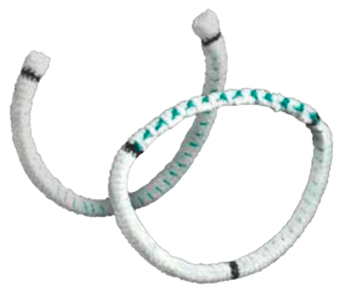

TAILOR

The Tailor™ Flexible Annuloplasty Ring and Band ARE FLEXIBLE AND ADAPTABLE TO SUSTAIN PHYSIOLOGIC MOVEMENT

The Tailor™ Flexible Annuloplasty Ring and Band are designed to maintain the size of a repaired mitral or tricuspid annulus while sustaining physiologic movement.

THE TAILOR RING PROVIDES A CUSTOMISABLE DESIGN

- Anterior and posterior support allows dynamic annular motion during the cardiac cycle

- Full, flexible ring can be tailored to address specific patient need

TAILOR BAND OFFERS A SIMPLE ALTERNATIVE FOR TRICUSPID VALVE REPAIR

- Standard pre-cut C-band provides time-saving simplicity

- Posterior support allows dynamic annular motion

- Band provides an alternative for tricuspid valve repair